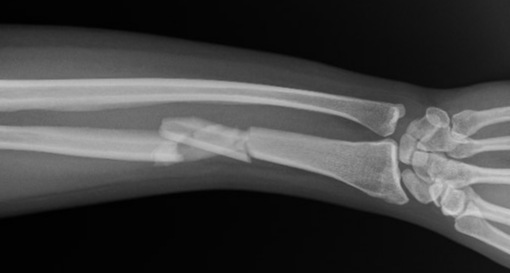

This is a simple “buckle” fracture of the end of the radius, also called a “torus” fracture.